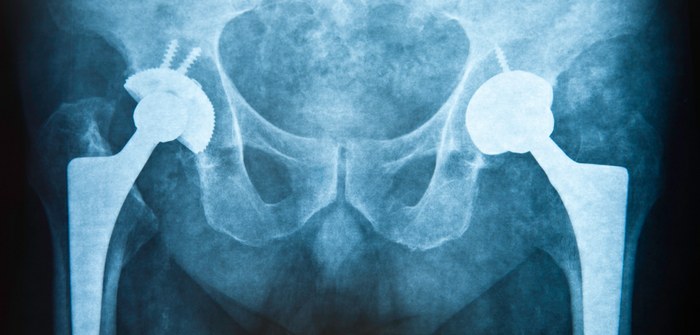

Nothing Sticks to a new Bioinspired coating for medical devices

Putting things in the body can be tricky, I mean we need things from joint replacements to cardiac implants and dialysis machines, these medical devices are needed to enhance or save lives on a daily basis. However, any device implanted in the body or in contact with flowing blood faces two critical challenges that can threaten the life of the patient the device is meant to help: blood clotting and bacterial infection. Problems that sound easier to fix than they actually are.